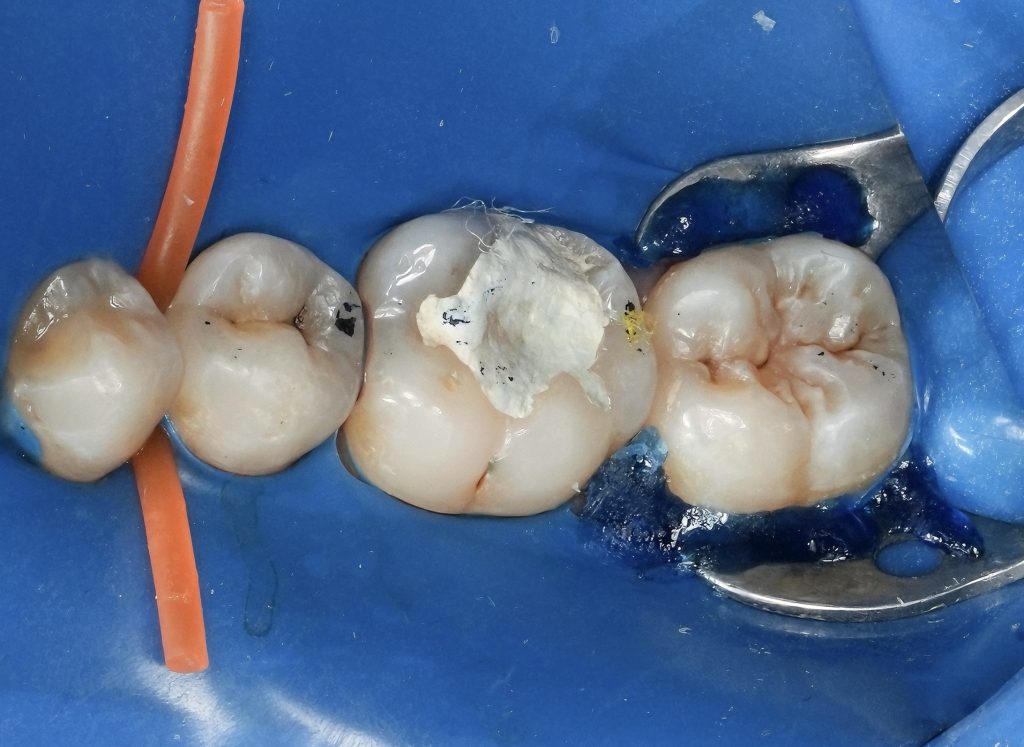

Endo-Restorative Interface

Immediately following obturation, attention was directed toward sealing the coronal aspect of the tooth. The endodontic access was refined into a restorative cavity, and adhesive protocols were implemented to reduce microleakage and prevent coronal reinfection. Immediate dentin sealing played a key role in preserving bond strength and pulpal floor integrity.

Biomimetic Direct Composite Restoration

The tooth was restored using a biomimetic direct composite technique. Incremental layering was employed to reduce polymerization stress and recreate natural occlusal anatomy. Cuspal reinforcement was achieved through bonded composite coverage rather than full-coverage crowns, allowing maximal preservation of sound tooth structure while restoring strength and function.

Outcome and Prognosis

The final restoration demonstrated proper occlusal form, functional harmony, and a secure coronal seal. Radiographic evaluation confirmed stable obturation without signs of periapical pathology. By integrating endodontic and restorative phases into a single biologically driven workflow, the tooth was returned to function with an optimized long-term prognosis.